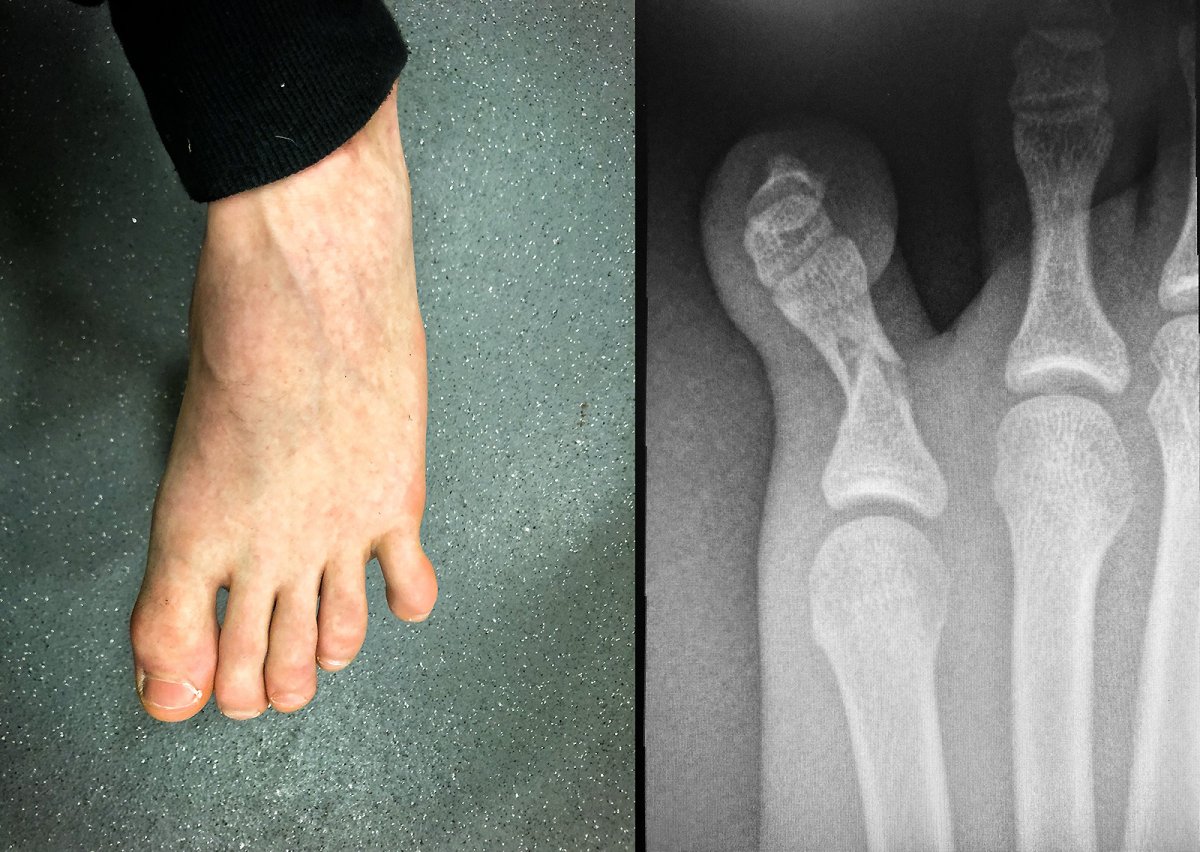

last night at feet jeet kune do, maximum broke his toe

ouchy ouchy